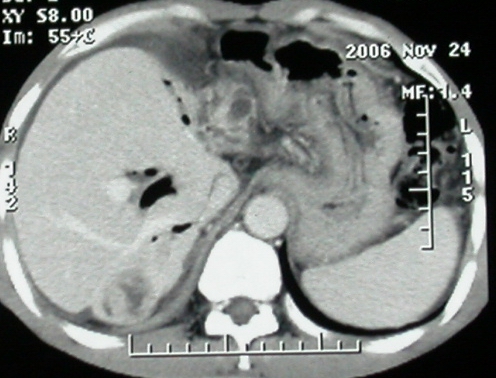

影像表现:胆囊扩张、肝内胆管不扩张,且见肝脏内树枝样气体影;十二指肠后方等密度占位,中心有不规则囊变区。增强实质部分轻度强化。下部腔静脉未强化------有栓子吗?

1、胰头部占位:胰管轻度扩张(可疑双管征),主要考虑恶性肿瘤,胰头癌?十二指肠间质瘤?后腹膜肿瘤?

2、门静脉高压症,主要考虑胰头部肿块压迫或者浸润所致肝前性门静脉主干受压;肝功能尚可,脾脏不大,无脾亢;

3、胆囊积液、肝胆管积气、胆道扩张伴有胆道感染;

4、右肝后上段占位(考虑肝胆管结石伴肝组织萎缩?)

5、下腔静脉受压;

6、左半肝缺失,原因不明?